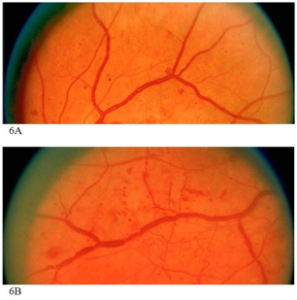

静脉袢

静脉袢 (venous loop) 是小静脉骤然偏离其正常路径的弯曲,提示糖尿病视网膜病变已经达到了一定的程度。

静脉串珠

静脉串珠(VB)是静脉管径的局部扩增,有时呈现串珠状,是糖尿病视网膜病变的典型特征。

静脉管径的弥散性增粗不被认为是静脉串珠。